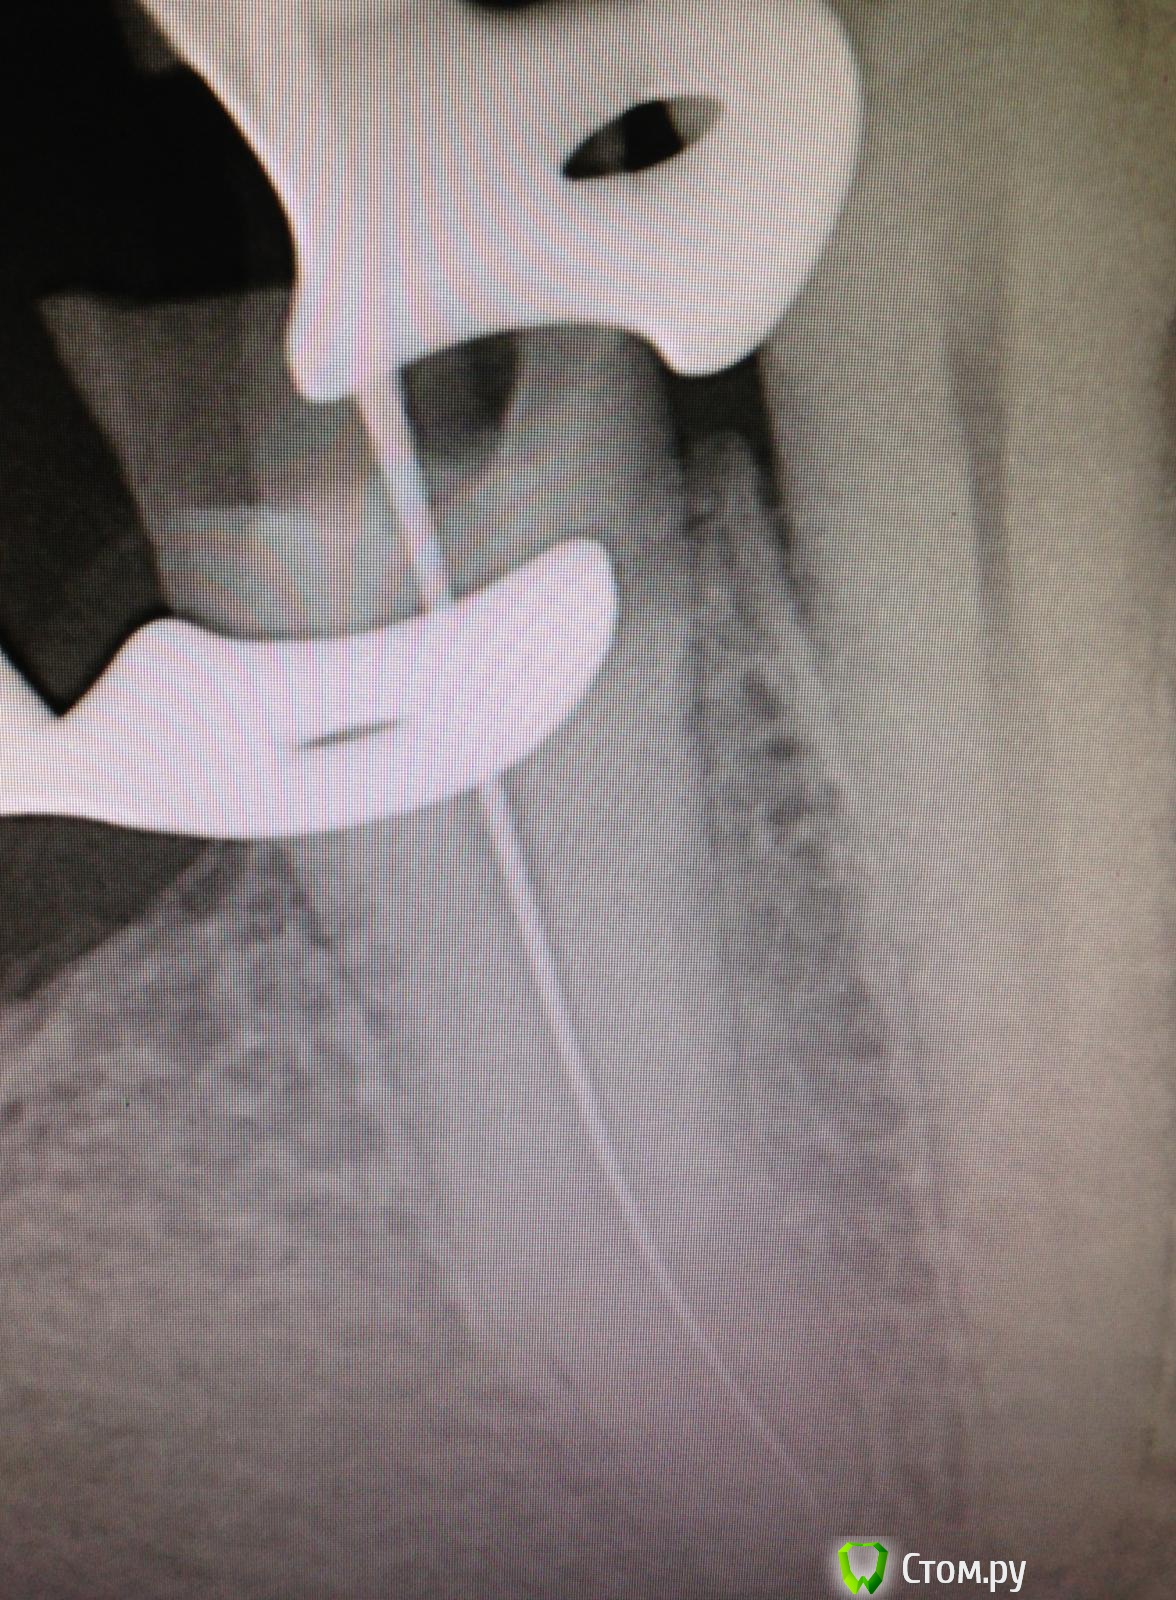

SSTi Опубликовано 20 октября, 2014 Автор Поделиться Опубликовано 20 октября, 2014 45. Пульпит. Латералька прикольная получилась. 3 Ссылка на комментарий

SSTi Опубликовано 22 ноября, 2014 Автор Поделиться Опубликовано 22 ноября, 2014 26. Хронический апикальный периодонтит. Пропущенный мб2. Зуб лечили год назад в гсп. Платно. И весь год он болел. Постоянные слабые боли. Переуссия +. 1 визит - коффердам, доступ, распломбировка мб, дб, небного. Поиск мб2. Обработка 4 каналов - протейпер д2,д3, профайлы - небный до 45.04. , мб и дб до 35.04, мб2 до 30.04. Гипохлорит, эдта, хлоргексидин, уз. Кальций. 2 часа. Второй визит - болей нет. Переуссия б/б. Вымыли кальций, еще моемся долго, латералка ( ан+ ). 2 часа. Ссылка на комментарий